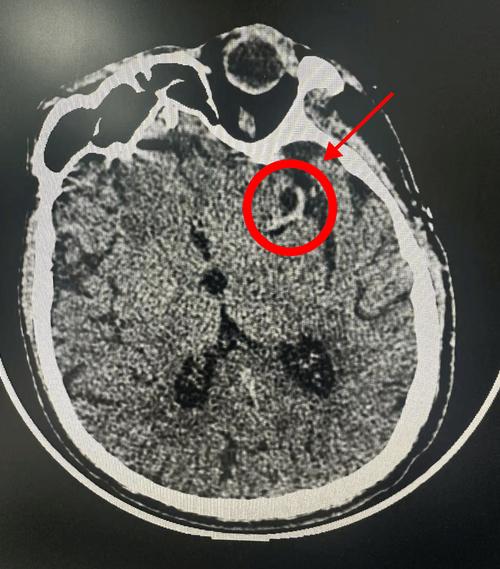

- 梗死灶太小:如果梗死的范围非常小(即所谓的“腔隙性脑梗死”),尤其是在脑干的深处,普通CT可能难以分辨,会被正常脑组织掩盖。

- 梗死灶位置特殊:某些部位的梗死,特别是小脑或脑干的梗死,在常规的头部CT平扫中可能不典型,容易漏诊。

- 层厚:如果CT扫描的层厚较厚,可能会遗漏小的病灶。